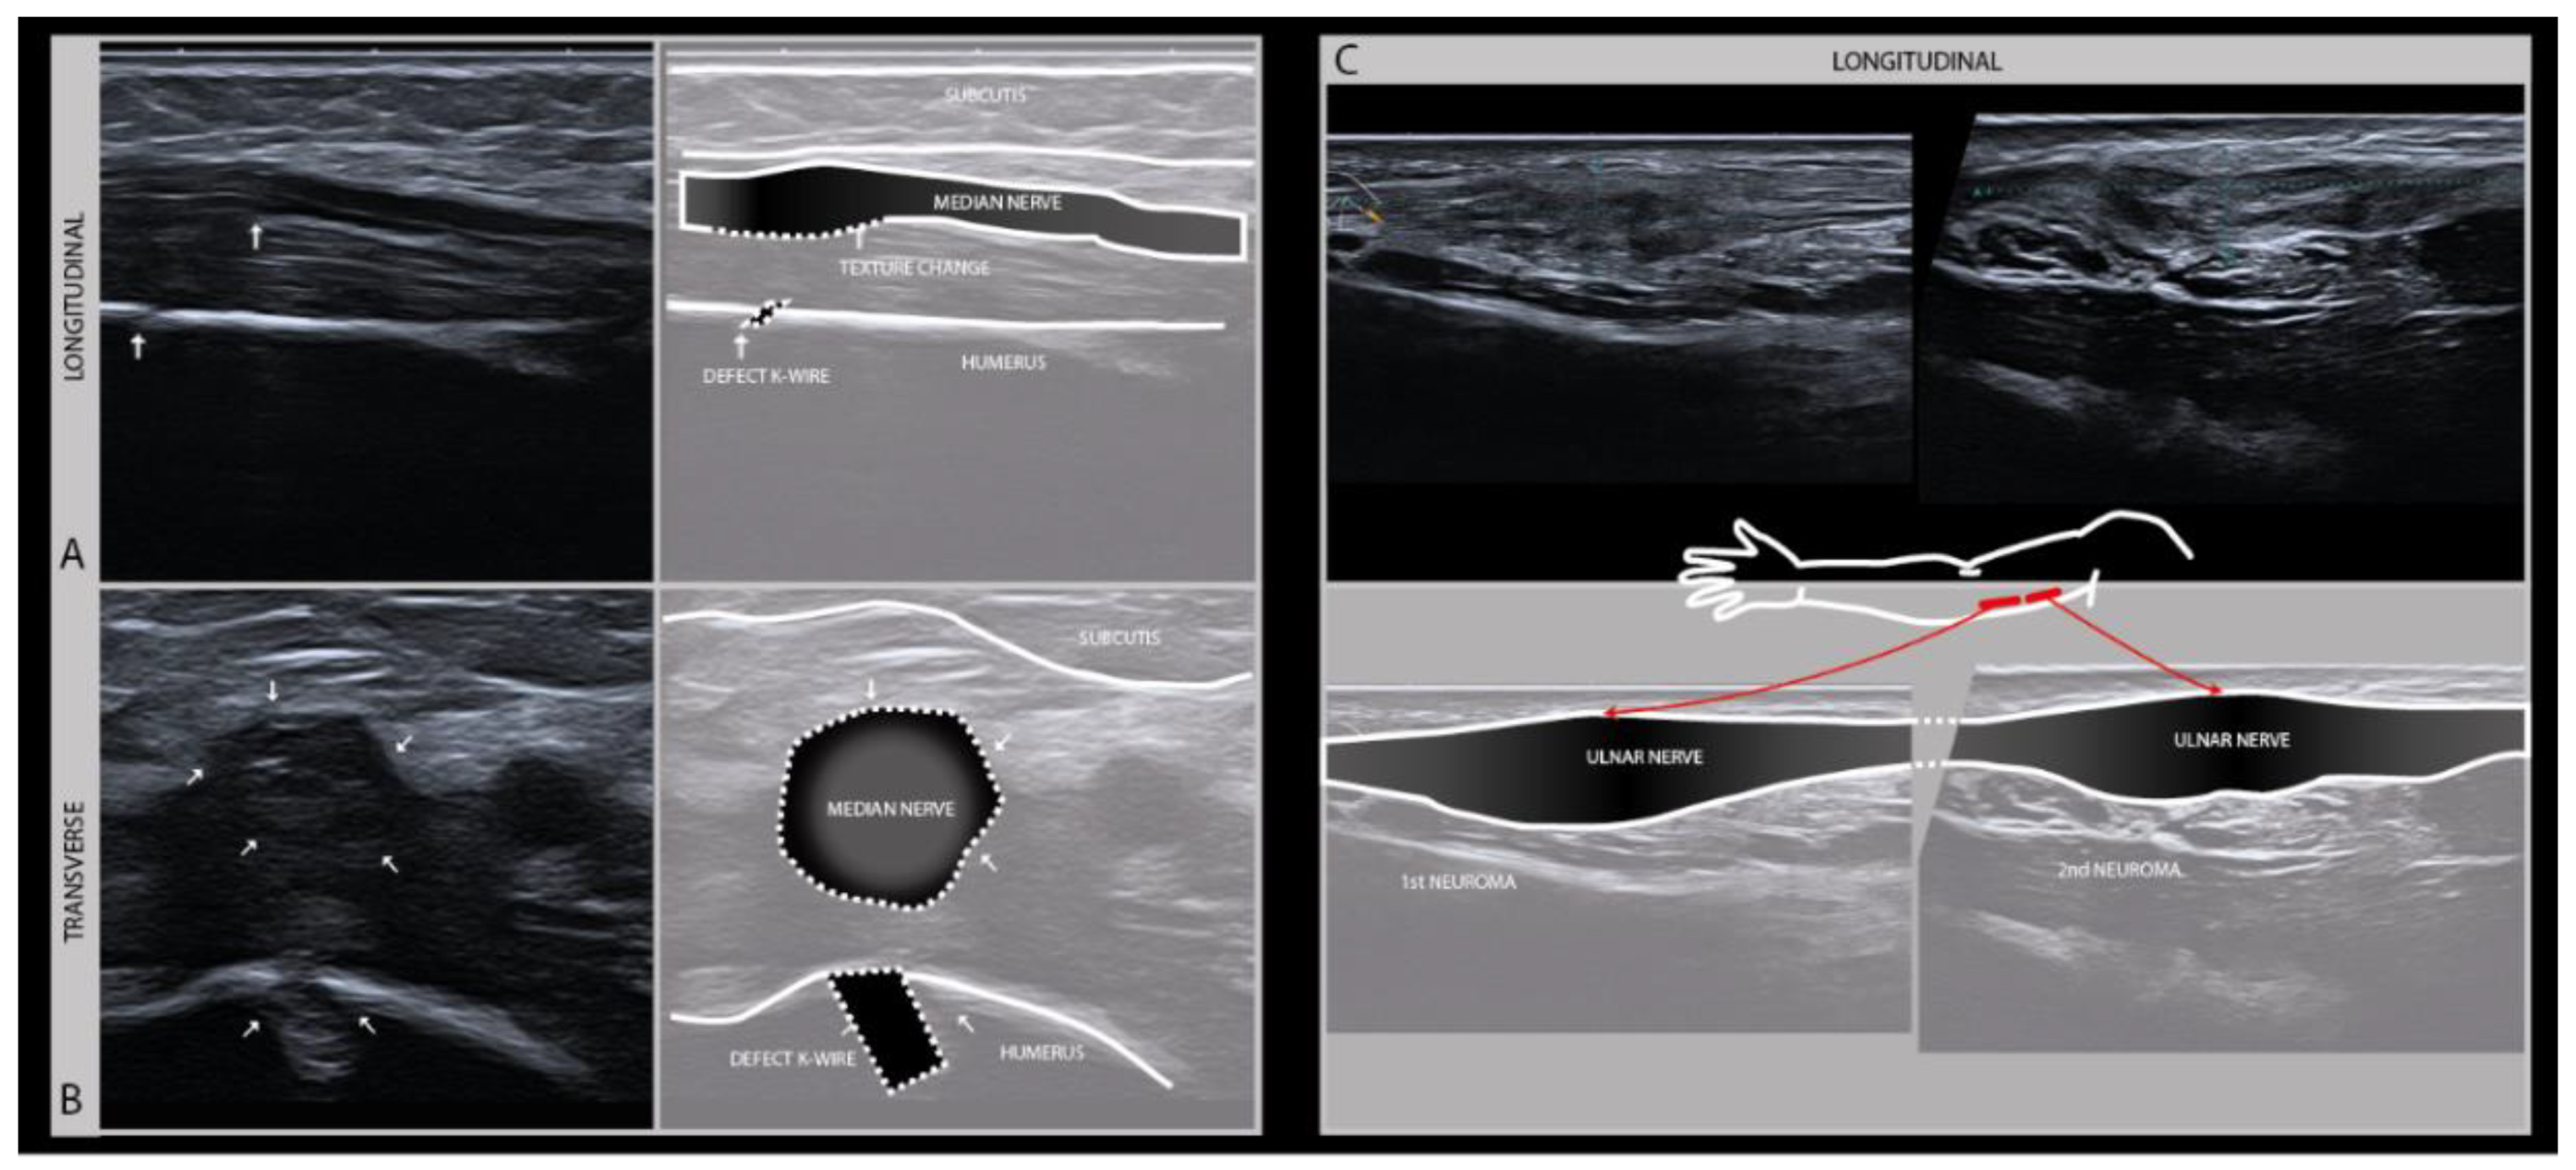

The therapeutic window for nerve surgery depends on an accurate assessment of the extent of the damage, which can usually be done clinically and may be augmented by EMG, localizing the exact site of the lesion and hence the distance between the lesion site and the affected muscle and skin, and detecting morphologic alterations of the damaged nerve that indicated transection or intraneural scarring (Figure 5). This information will guide surgical decision making by assessing the regenerative potential [25].

Figure 5.

Longitudinal (A) and transverse (B) images of the left median nerve in the distal upper arm of a 5-year-old boy with a supracondylar humerus fracture surgically treated with K-wire fixation. The subsequent median nerve lesion with a change of nerve architecture seen near the bone defect after K-wire removal (high frequency probe 19–24 MHz). Full recovery within weeks after K-wire removal. Longitudinal (C) images of the ulnar nerve in the upper arm with two serial neuromas after a local gunshot wound.